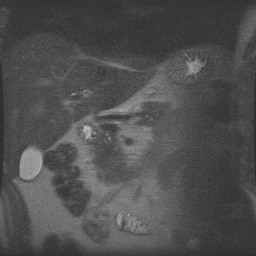

Abdomen